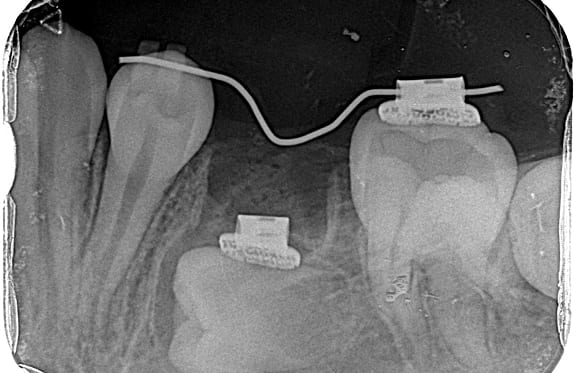

● C4を超え歯根までの虫歯を抜歯、スペースを利用して歯並び全体を整えた症例

藤沢デンタルオフィスの虫歯や破折で抜歯後の部分矯正